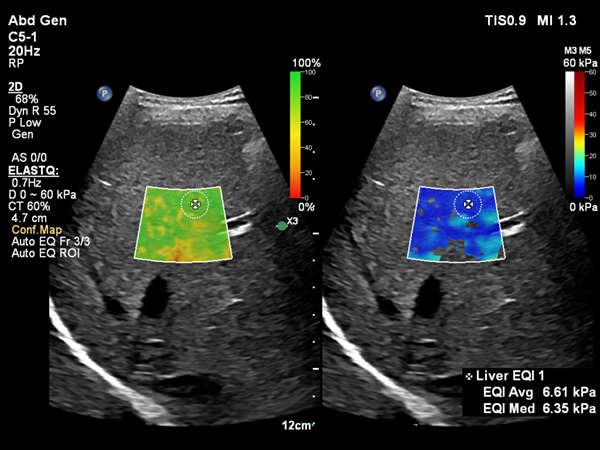

肝硬度測定ElastQの自動化機能搭載

Shear Wave Elastographyを使用して肝臓の硬さを非侵襲的に計測するアプリケーションElastQに,自動化機能が追加されました。Auto ElastQは,計測に適したフレームやROIポジションを自動で判別し,計測結果を表示することが可能です。これにより,これまで課題であった検査時間を最大60%短縮し2,99%の再現性が報告されています。3

2 D001795093, Marketing Claims Evidence for Auto ElastQ timing, V12.0_Rev.A

3 D001705221,Auto ElastQ clinical study report